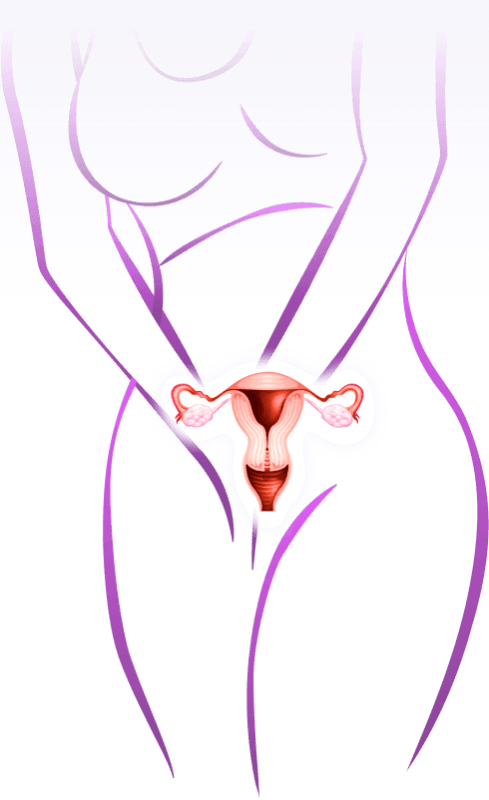

Nguyên nhân

viêm nhiễm vùng kín và hậu quả

Không vệ sinh vùng kín thường xuyên, mặc quần áo bó sát

Vệ sinh vùng kín bằng các chế phẩm từ hóa chất

Mất cân bằng nội tiết

Quan hệ tình dục không lành mạnh

Ngứa ngáy, hôi hám

Kinh nguyệt không đều

Xuất huyết âm đạo

Khô hạn âm đạo

Tiểu rắt, tiểu buốt

Tạo u, khối

Ảnh hưởng đến khả năng sinh sản

Lây viêm nhiễm cho thai nhi